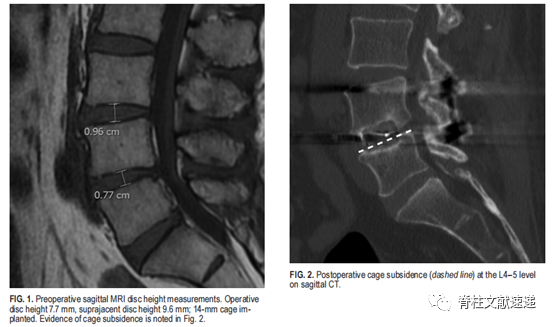

图注:左图为患者术前MRI结果,可以看出患者手术节段(L4/5)椎间隙高度为0.77cm,手术节段邻近的上一节段(L3/4)椎间隙高度为0.96cm,术中选中Cage的高度为1.4cm。右图为该患者术后复查时的CT结果,可见观察到患者术后发生了Cage下沉。